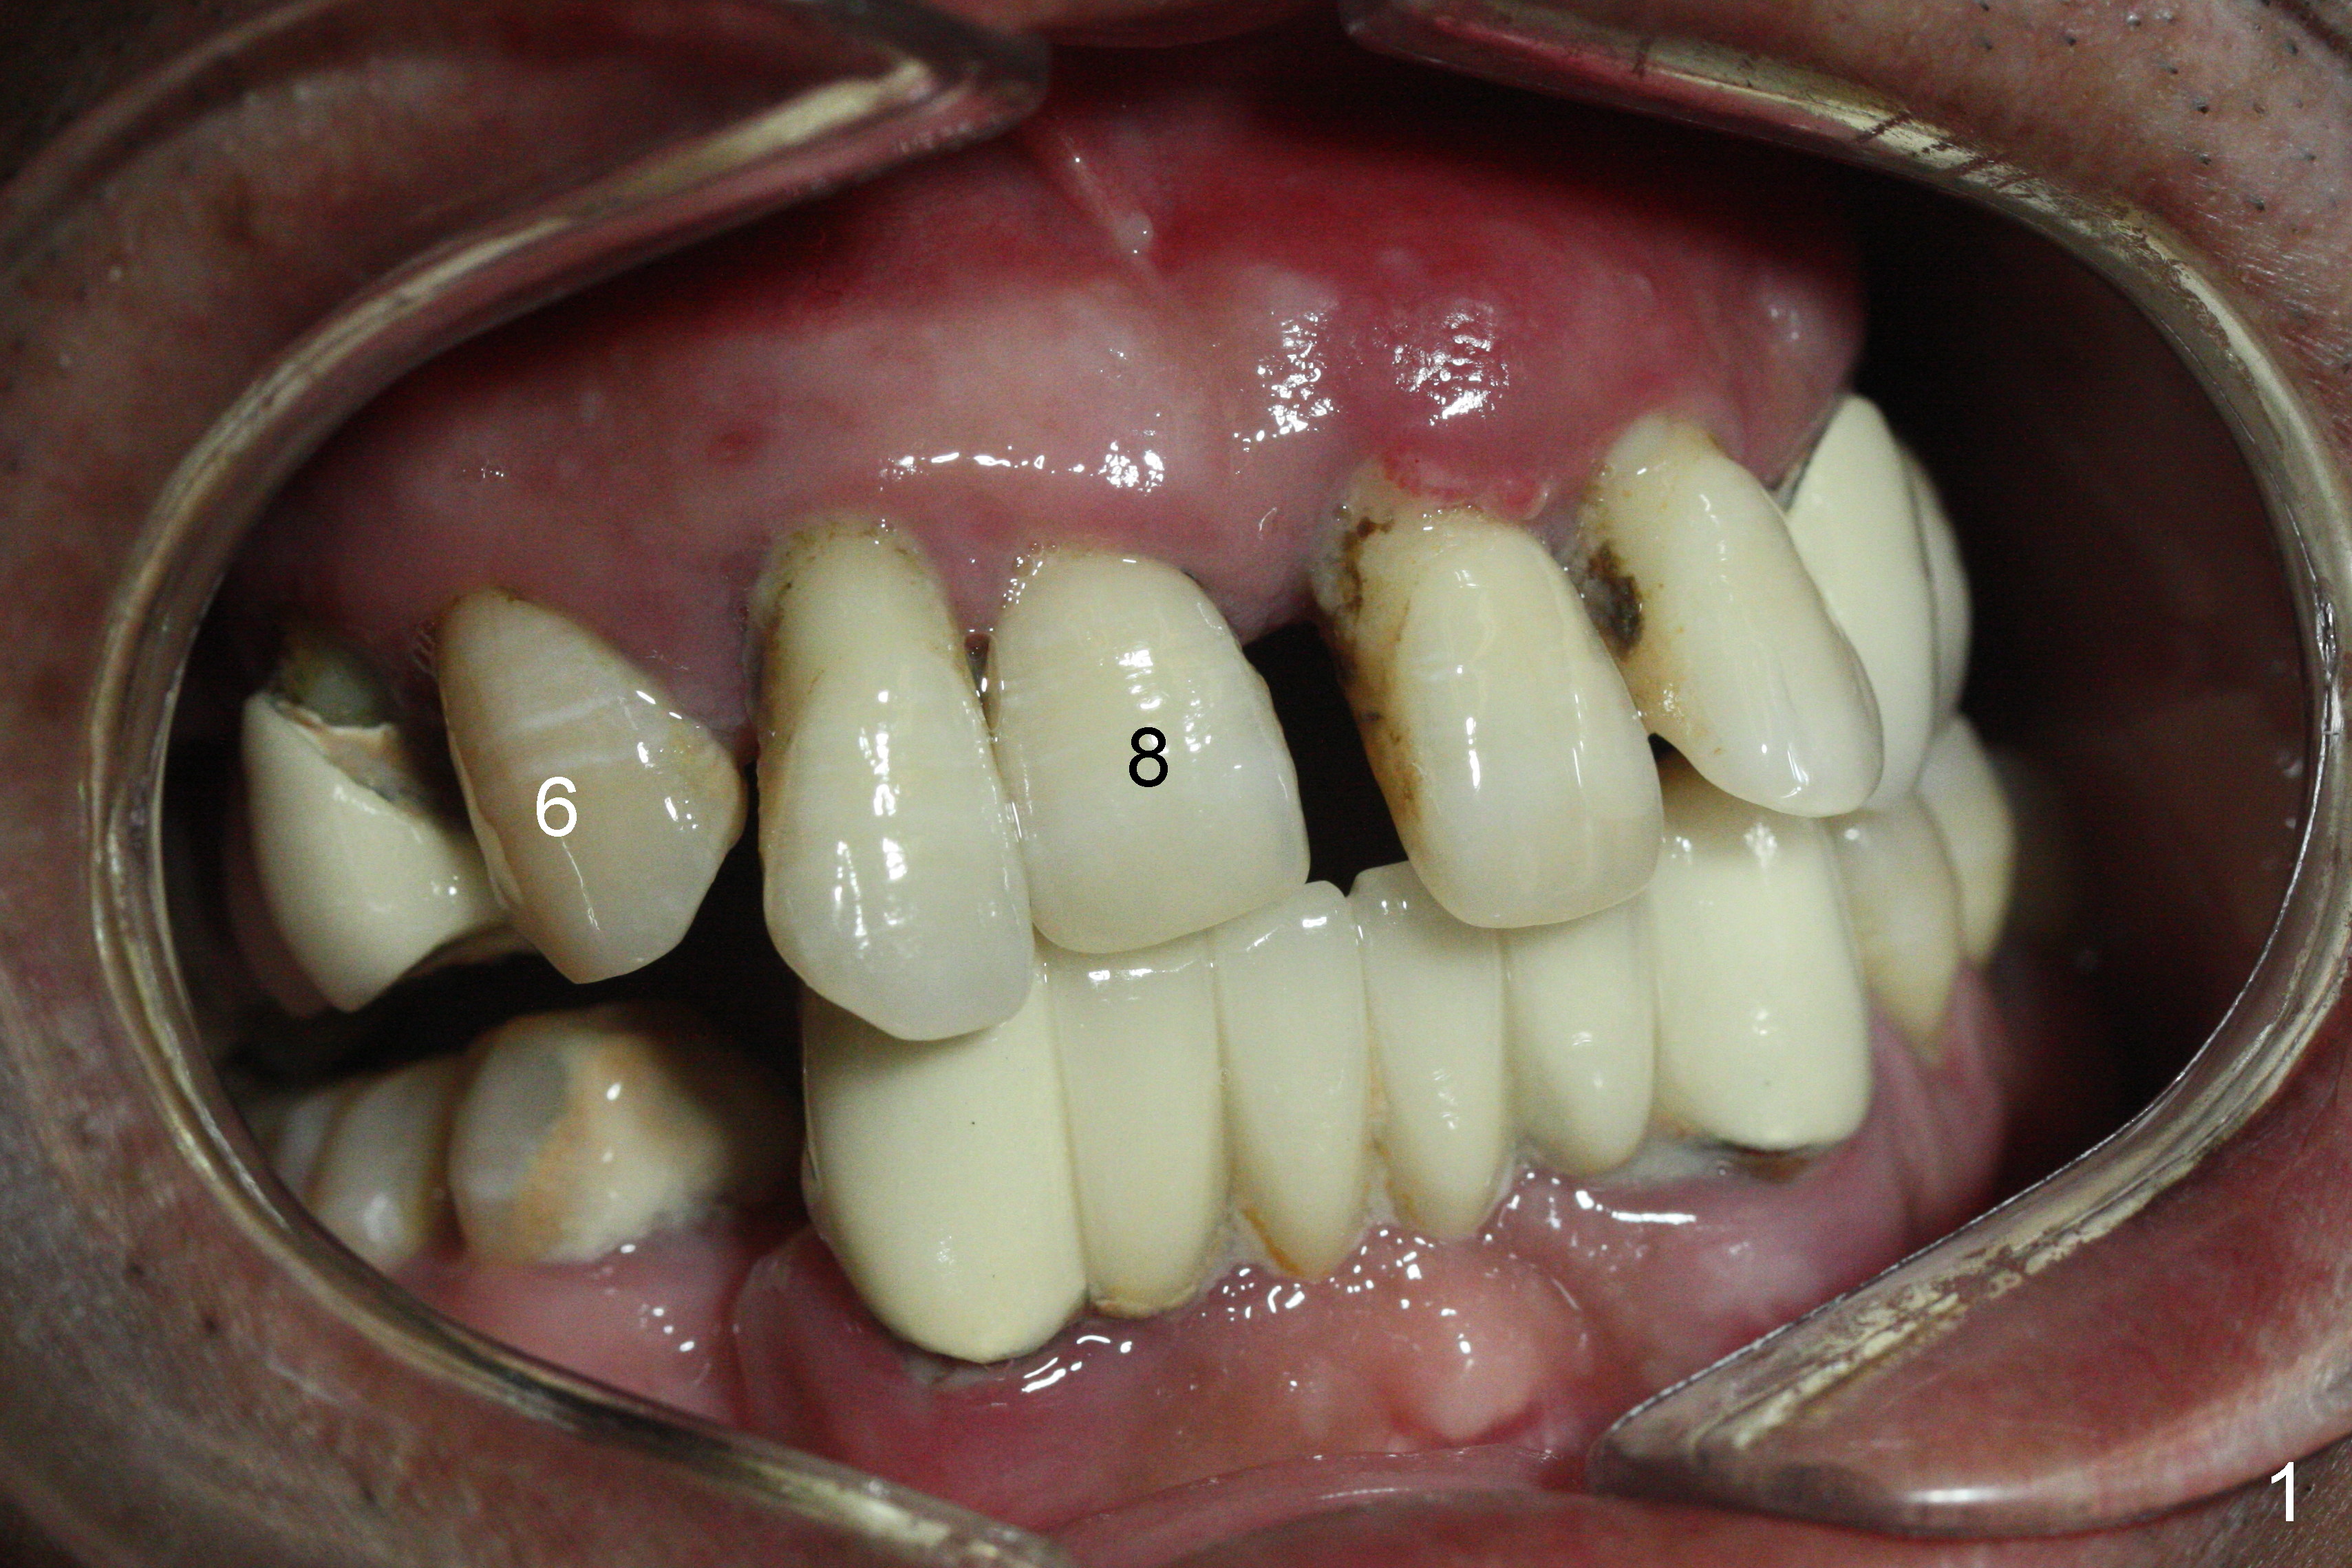

The dentition is poor except #6 and 8 (Fig.1). The gingiva is erythematous at #9-11 (Fig.2). The teeth #9 and 10 are extracted first; a 4x16 mm UF implant is placed at #9, while a 2 mm pilot drill is at the site of #10 (Fig.3). The implant at #9 is placed deeper with placement of 4.5x5.5(5) mm abutment; a 3.8x15 mm implant is placed at #10 initially (Fig.4). While the latter is placed deeper, a 4x16 mm implant is placed at #11 (Fig.5 after removal of #11-15 FPD (fixed partial denture)). In fact the trajectory at #11 is not difficult to be changed with 2 mm drill (Fig.6). After use of 3 mm drill, the implant is reinserted at #11 with ideal trajectory (Fig.7). After further seating of the implant at #11, graft is placed in the remaining sockets of #9-11 (Fig.8 *; later more graft is placed mesial to #11 implant (^)). Finally, a 4.5x7(5), 4.5x15° B (4) and 5.5x7(5) mm abutments are tightened and prepared (Fig.9) for splinted provisional at #9-10.